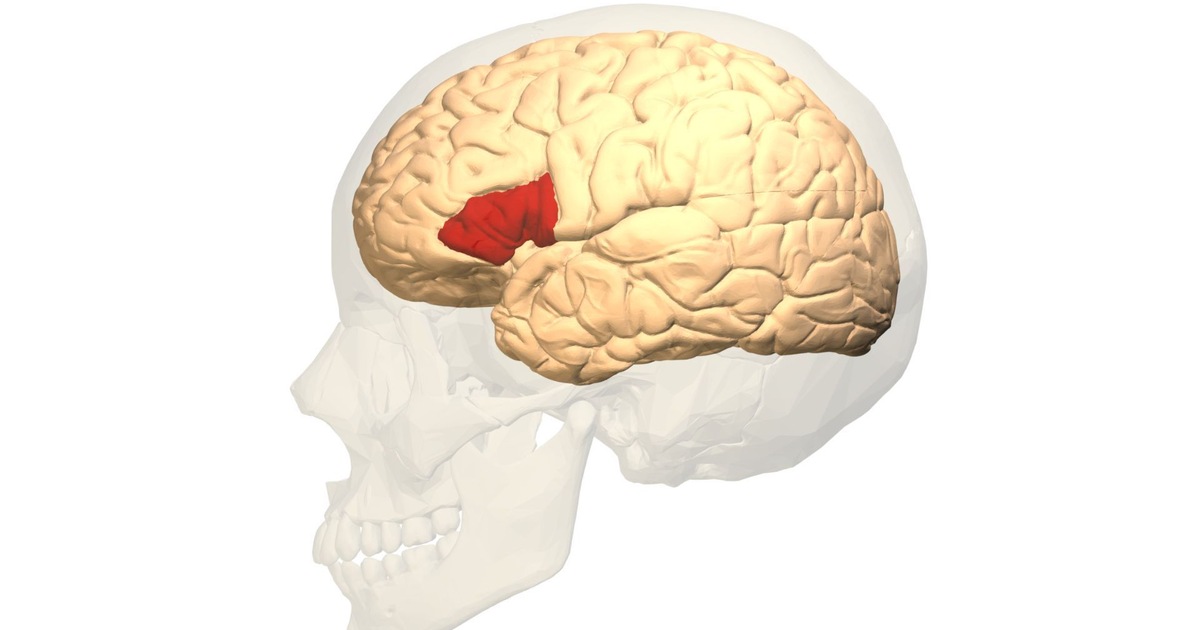

Após a morte de Leborgne, Broca realizou uma autópsia e encontrou uma lesão significativa no lado esquerdo do cérebro, especificamente no lobo frontal.

Essa descoberta levou a uma conclusão revolucionária: a fala não era uma função espalhada pelo cérebro, mas sim localizada em uma região específica.

O nascimento da Área de Broca

A região identificada passou a ser conhecida como Área de Broca, responsável pela produção da linguagem. Danos nessa área causam a chamada afasia de Broca, onde a pessoa entende o que é dito, mas tem dificuldade para falar.

Essa descoberta foi uma das primeiras provas concretas de que funções cerebrais são localizadas — um conceito essencial na neurociência moderna.